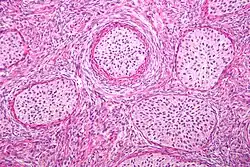

Micrograph of a Walthard cell nest, the entity Brenner tumours are thought to arise from. H&E stain.

Histologically, there are nests of transitional epithelial (urothelial) cells with longitudinal nuclear grooves (coffee bean nuclei) lying in abundant fibrous stroma.

The coffee bean nuclei are the nuclear grooves exceptionally pathognomonic to the sex cord stromal tumour, the ovarian granulosa cell tumour, with the fluid-filled spaces Call–Exner bodies between the granulosa cells.[4][5]